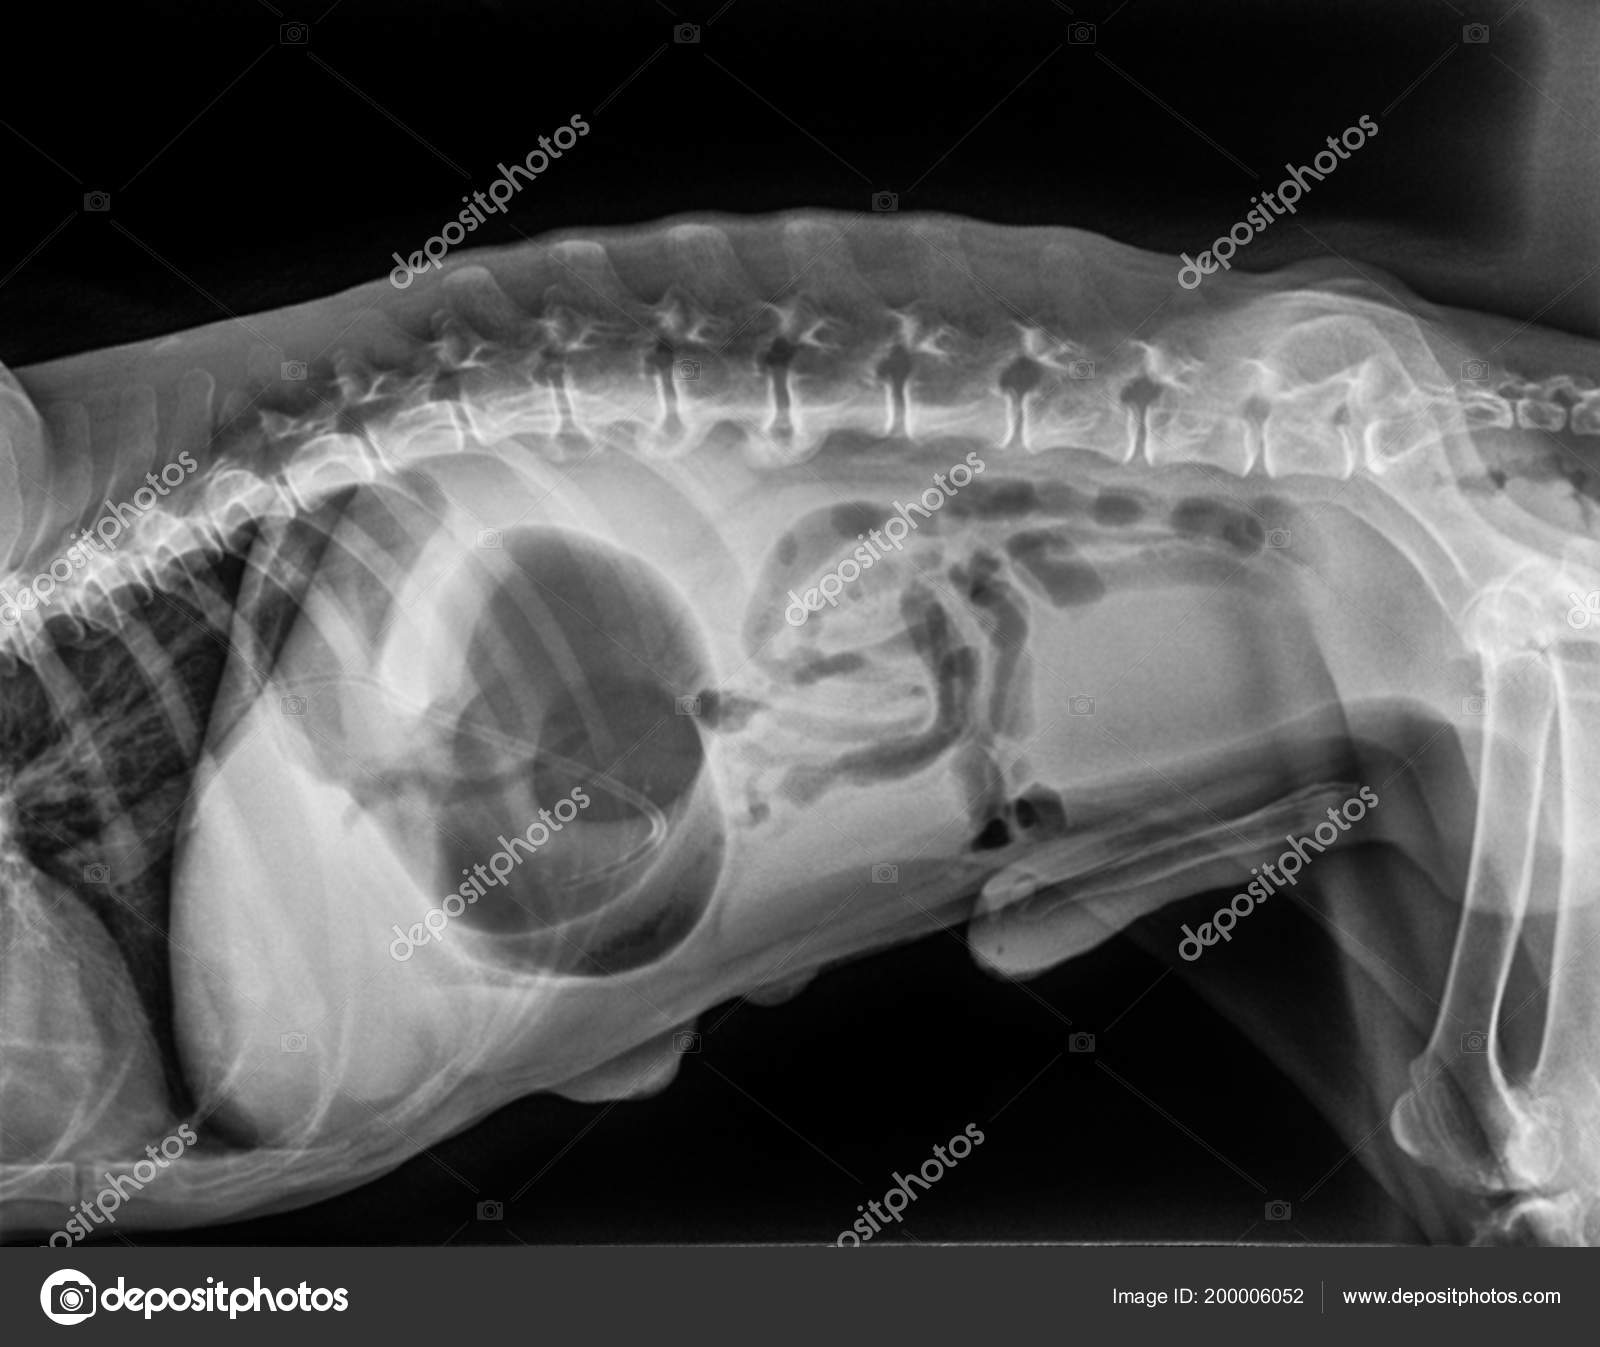

Но даже если проглоченный собакой предмет благополучно миновал пищевод, он может застрять в желудке и даже в кишечнике.

При проникновении небольших инородных предметов в желудок симптомов практически нет, и они могут находиться там достаточно длительное время. Только при сильном раздражении слизистой, наличии эрозии или язвы желудка у собаки возникает рвота (как пищевыми массами, так и желудочным соком).

Иногда инородные предметы, попадая в пищеварительный тракт, проходят пищевод и желудок, а затем останавливаются в кишечнике.